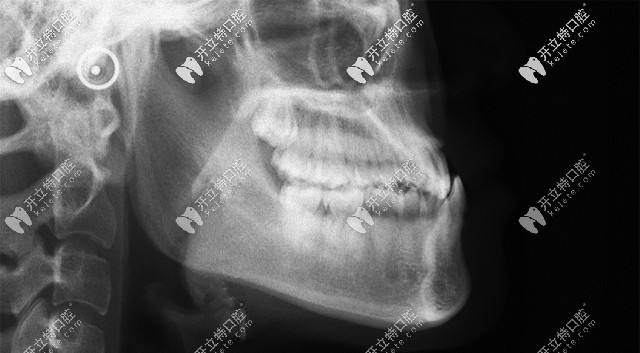

從這張頭顱側位片,可以清晰的看到顧客牙齒情況是骨性反頜(地包天)▲